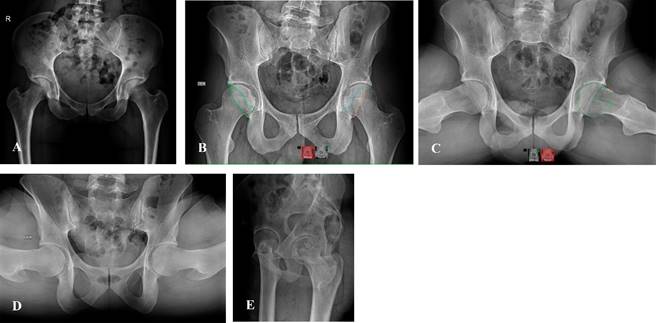

La evaluación de la cadera se realiza mediante seis proyecciones: AP o anteroposterior, falso perfil de Lequesne, lateral pura o cross-Table, proyección de Lowenstein (frog-leg) y las dos proyecciones de Dunn 45o y 90o; sin embargo, no todas se realizan de rutina inicialmente.

Las que nosotros recomendamos de manera sistemática son proyecciones anteroposterior en bipedestación, de Lequesne, Dunn a 45o y eje mecánico bipodálico. Con estas proyecciones podemos evaluar a la articulación coxofemoral en los tres planos anatómicos, es decir, en coronal, axial y sagital, brindándonos una perspectiva tridimensional de la articulación. Con el eje mecánico bipodálico, podemos evaluar las articulaciones de la rodilla y tobillo; asimismo, conocer la distribución de cargas, discrepancias y su impacto en la articulación coxofemoral (Figura 8).

Figura 8: A y B) Radiografía anteroposterior en bipedestación de pelvis. C) Proyección de Dunn a 45o. D) proyección a 90o. E) Proyección de Lequesne de cadera derecha o falso perfil.

La evaluación inicial por imagen debe incluir radiografía anteroposterior (AP) con apoyo y el falso perfil, el resto de las proyecciones específicas se solicitan de acuerdo con nuestra sospecha diagnóstica.

Para evaluar una radiografía AP adecuada tomamos como referencia la alineación de la sínfisis del pubis y coxis en el mismo plano y con una distancia entre ambos de 1-3 cm, simetría en ambos agujeros obturadores, crestas ilíacas y de ambos trocánteres menores, que son indicativos de correcta rotación interna de 15 a 20o, para evaluar de manera correcta en ángulo cérvico-diafisario de la cadera.

En la radiografía anteroposterior verdadera, podemos evaluar las distintas estructuras anatómicas, iniciando por las líneas acetabulares, la línea ilioisquiática, iliopectínea, las paredes acetabulares, en las que podemos identificar múltiples patologías como versiones, o bien datos o signos sugestivos de pinzamiento como el signo de crossover (Figura 9), donde la pared anterior y posterior se interceptan formando un «ocho». La sobrecobertura global se puede identificar con la relación de la línea iliopectínea y la escotadura acetabular (lágrima de Kohler), en donde la fosa debe ser lateral a esta línea; de no serlo, estamos ante una sobrecobertura femoroacetabular.7

Mediciones especiales

En esta proyección podemos valorar el ángulo Wiberg o centro borde (Figura 9A), indicativo de cobertura lateral, el cual se traza del centro de rotación de la cadera y la porción más lateral del acetábulo, cuyo valor normal es de 25 a 40o.

Otro ángulo de importancia para la sobrecobertura o descobertura acetabular es el índice acetabular o de Tönnis cuyo valor normal lo encontramos en 0 a 10o (Figura 9C).

Ángulo cervicodiafisario: cuyo valor normal es de 135-145o; > 145o se considera coxa valga, < de 135o coxa vara.

Ángulo de Sharp: formada por una línea inferior a ambas lagrimas acetabulares y línea que pasa por el extremo del borde acetabular lateral, determina la inclinación acetabular, cuyo valor normal es 40-45o.7

Índice acetabular de profundidad: se determina a través de una línea que une la porción superolateral e inferomedial del acetábulo entre la profundidad del mismo determinada por una línea perpendicular a la anterior en su porción media hasta el fondo acetabular, multiplicado el mismo por 1,000.2

Las proyecciones de Dunn a 45o y 90o de flexión, rotación externa de 45o y abducción de 20o son proyecciones específicas para valorar la esfericidad de cabeza femoral (importante para valoración de pinzamientos sobre todo tipo cam) y la unión craneocervical (Figura 10).7

Figura 10: Proyección de Dunn a 45o, medición de unión craneocervical, identificándose datos de pinzamiento tipo cam.

La radiografía de lateral o falso perfil de Lequesne, es de utilidad en la valoración de la morfología anterior de la cabeza femoral y su cobertura acetabular en la que se puede valorar el ángulo center edge de Lequesne y nos permite valorar la cobertura acetabular anterior, cuyo valor normal es de 25 a 35o (Figura 11).2

Figura 11: Proyección de Lequesne donde se puede valorar los cambios morfológicos de cabeza femoral y acetábulo en cadera derecha con sobrecobertura anterior del techo acetabular.